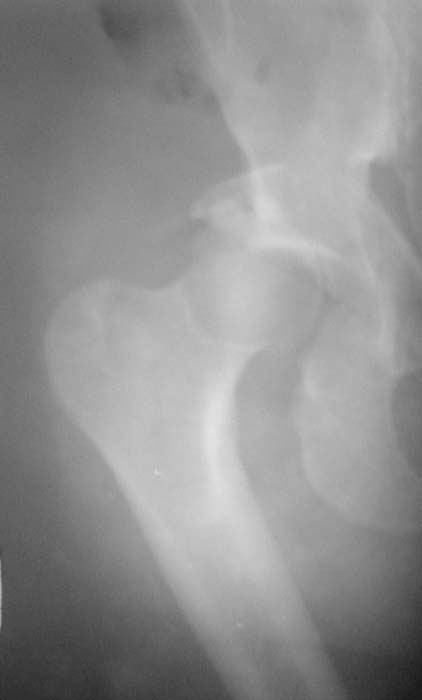

Уважаемые коллеги!Мужчина, 40 лет. Травма несколько месяцев назад. Получил закрытый вывих правого тазобедренного сустава и перелом вертлужной впадины (сним.1).Лечился скелетным вытяжением. Сейчас (сним.2) жалобы на боли, ограничение движений. Вопрос: тактика лечения (эндопротезирование и/или восстановительная операция, иное)?С уважением,А.В.Владзимирский

Вывих, похоже, вообще не был устранен. Или из-за дефекта заднего края сразу рецидивировал.